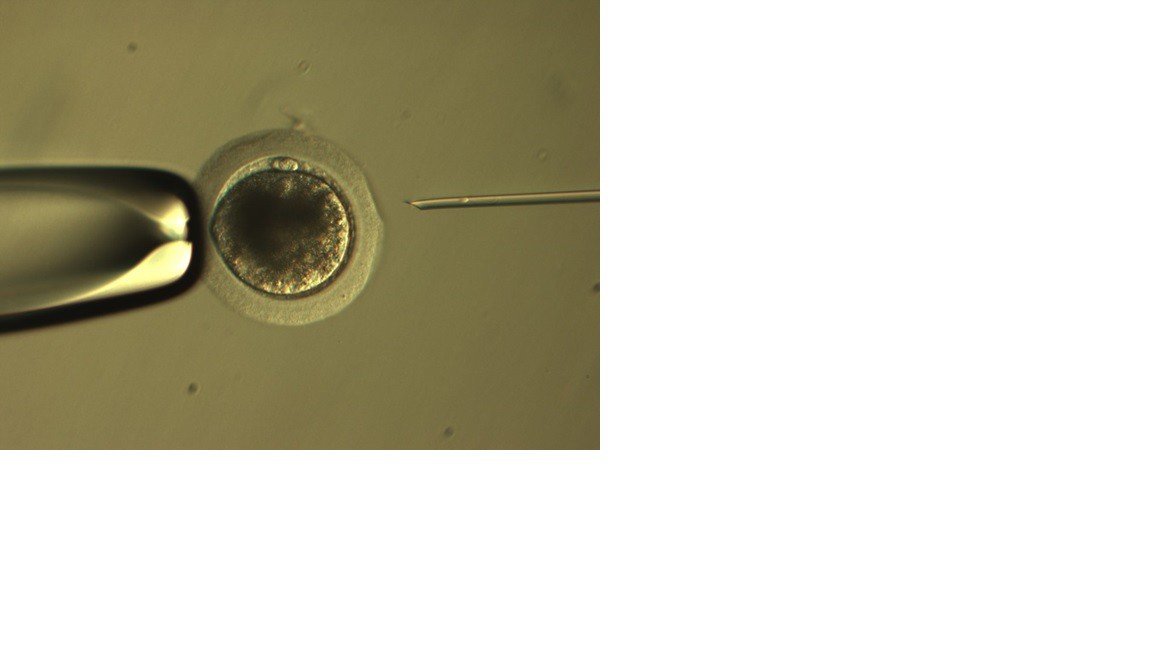

In vitro Produktion von Pferdeembryonen mit OPU und ICSI.